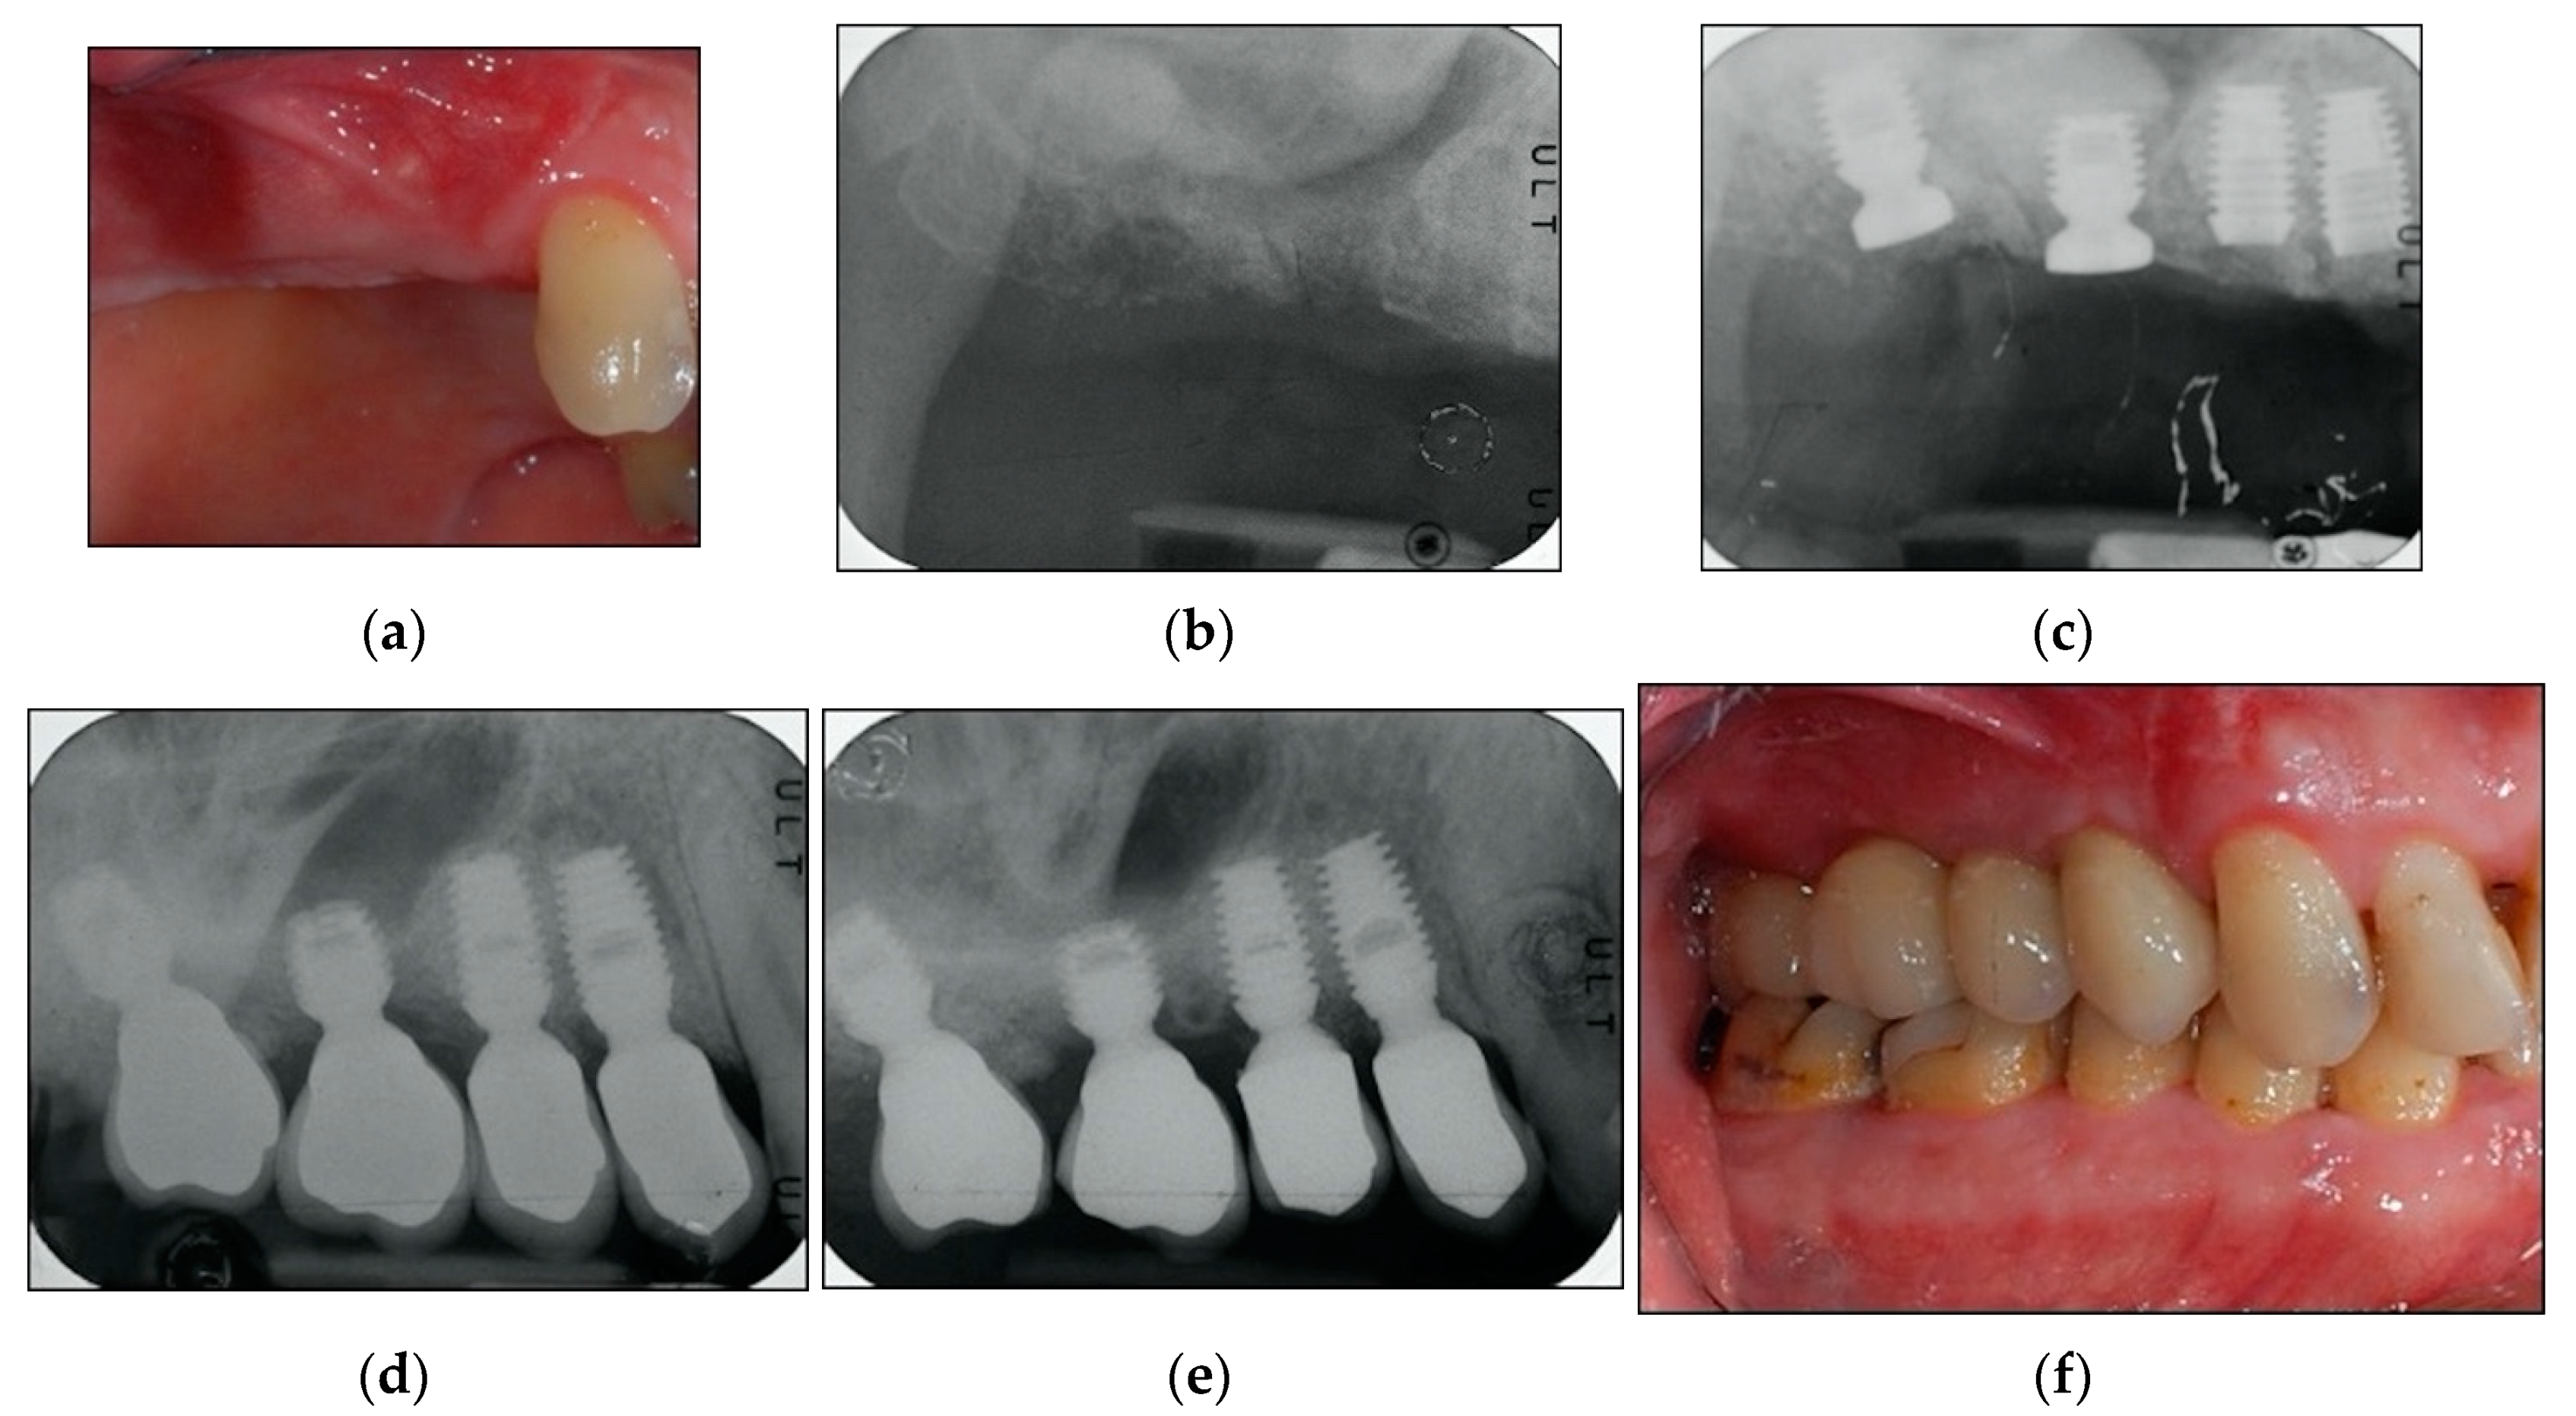

2.2. Surgical Protocol

2.3. Prosthetic Protocol and Follow-Up Evaluation